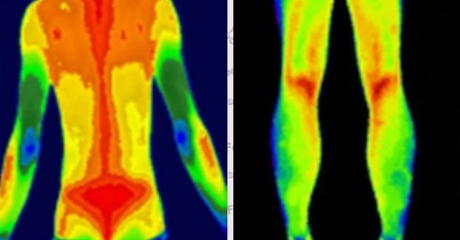

紅外熱像儀利用紅外輻射技術(shù),將物體散發(fā)的紅外輻射轉(zhuǎn)化為可見的熱圖。熱圖通過不同顏色的色彩表示不同的溫度區(qū)域,從而幫助我們觀察和分析物體表面的溫度分布情況。

- 溫度對比:通過觀察熱圖中不同區(qū)域的顏色差異,可以比較不同區(qū)域的溫度差異。高溫區(qū)域通常呈現(xiàn)為亮色或暖色調(diào),低溫區(qū)域則為暗色或冷色調(diào)。通過對比不同區(qū)域的溫度差異,我們可以快速發(fā)現(xiàn)異常情況。

- 熱點(diǎn)定位:熱圖中的亮色區(qū)域通常表示溫度較高的區(qū)域,這些區(qū)域可能存在潛在的問題或異常。通過定位和標(biāo)記熱圖中的熱點(diǎn),我們可以進(jìn)一步分析這些區(qū)域的原因和可能的解決方案。

三、色彩和溫度的對應(yīng)關(guān)系

熱圖中的色彩用于表示不同溫度區(qū)域,不同的紅外熱像儀廠商可能會采用不同的配色方案。一般而言,常見的配色方案有彩虹色、鐵紅色和黑白色等。下面是一個常見的色溫對應(yīng)關(guān)系表格,供您參考:

| 紅色 | 高溫區(qū)域 |

| 綠色 | 中溫區(qū)域 |

| 紫色 | 低溫區(qū)域 |